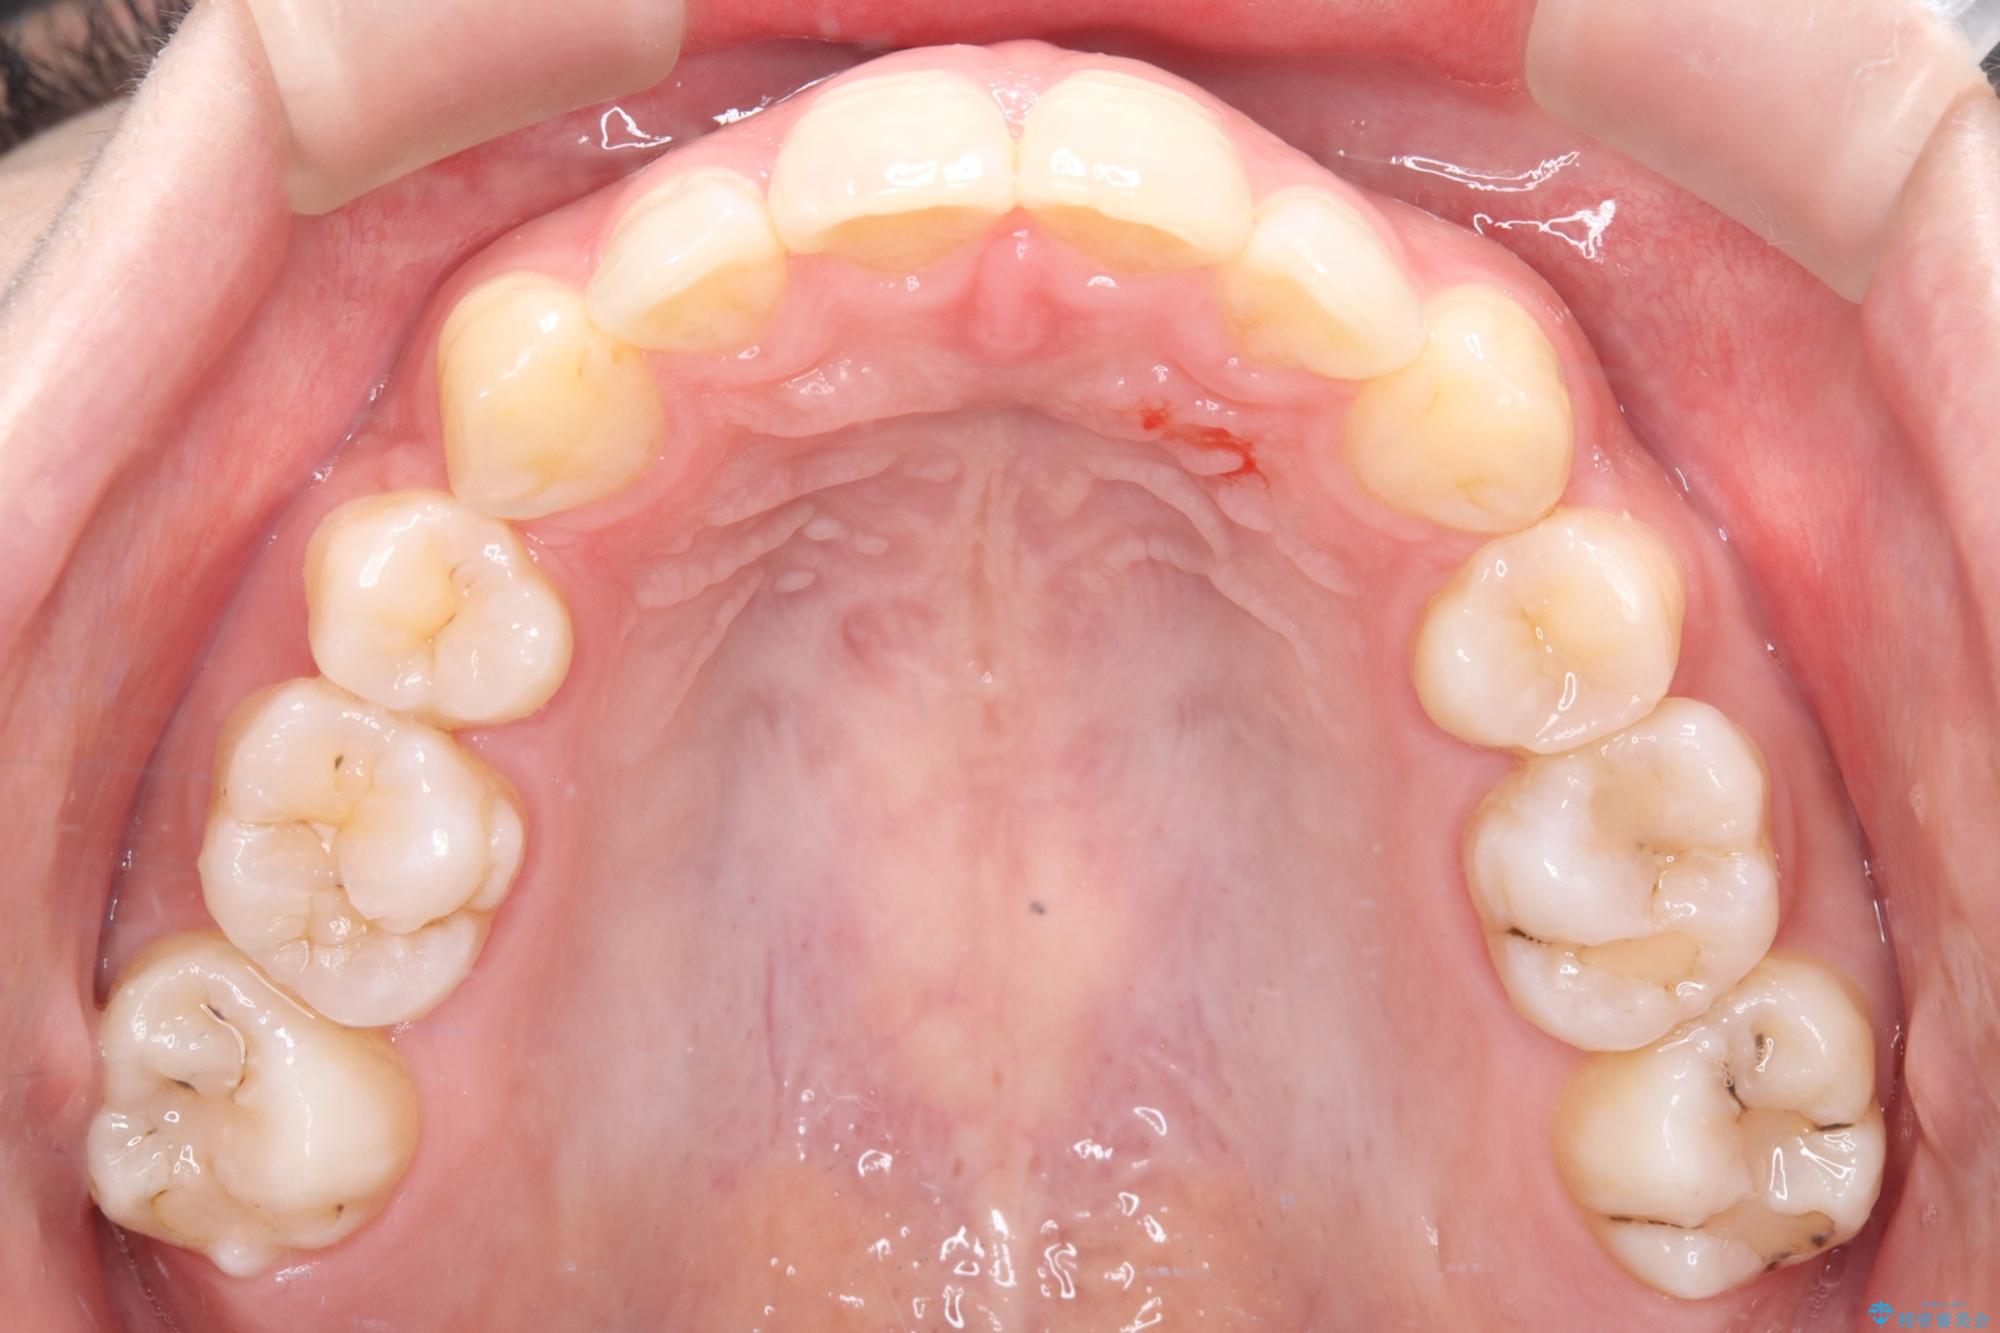

- 前歯から奥歯にかけて歯の重なりが激しい歯のがたつき(重度叢生)を主訴にご来院されました。精密検査の結果、歯が並ぶスペースが大幅に不足しており、歯並びを整え、口元を美しく引っ込めるためには、スペースの確保が必要と診断しました。そこで、上下左右の第一小臼歯(4番目の歯)を計4本抜歯し、そのスペースを利用して歯並び全体を整える抜歯矯正の治療計画を立案。装置には、透明で目立たないインビザラインを採用し、審美性と治療効果の両立を目指しました。

今回の治療では、重度の叢生を改善するため、まず計画通り上下左右4本の小臼歯を抜歯し、歯を並べるための十分なスペースを確保しました。装置には透明で取り外し可能なインビザラインを使用。抜歯によってできたスペースを最大限に活用し、マウスピースを定期的に交換しながら、デコボコを解消しつつ、前歯を効果的に後退させました。

治療の結果、長年の悩みであった重度の歯のがたつきが解消され、口元の突出感も改善。機能的にも安定し、審美的にも美しい、理想的な歯並びを獲得していただけました。